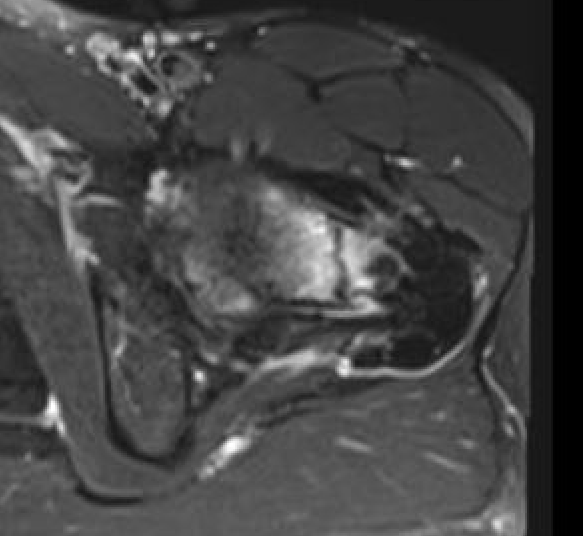

MRI

Edema / fracture line / hip effusion

MRI demonstrating edema likely across entire neck

MRI demonstrates complete fracture